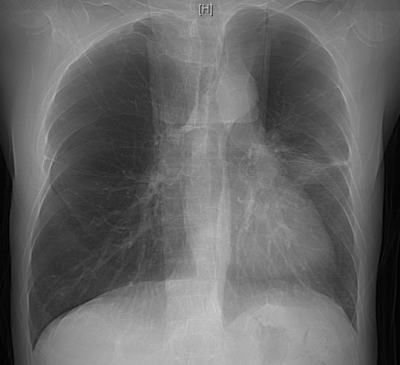

抱着最后一丝希望,李明章辗转至香港马会app 呼吸与危重症医学科救治。该科副主任朱锦琪、梁伟军及团队高度警觉免疫治疗病史可能带来的并发症,详细追溯他两年的免疫治疗用药记录,对其近期肺部CT影像进行反复对比和深入研判,认为其符合免疫检查点抑制剂相关肺炎(CIP)的典型表现,确诊其为迟发性、重度(4级)免疫检查点抑制剂相关肺炎。

免疫检查点抑制剂相关肺炎4级

明确诊断后,患者的治疗迎来关键转折点,团队迅速调整方案,启动大剂量糖皮质激素抗炎治疗,治疗效果立竿见影。患者的病情显著改善,氧合指数稳步上升,呼吸困难症状明显缓解。经过精心治疗,他在进入呼吸重症监护室一周后便转入呼吸科普通病房;10天后复查胸部CT,显示肺部弥漫性病变明显吸收好转,顺利出院。后续的定期随访复查也证实其肺部状况持续向好。

双肺病变持续吸收